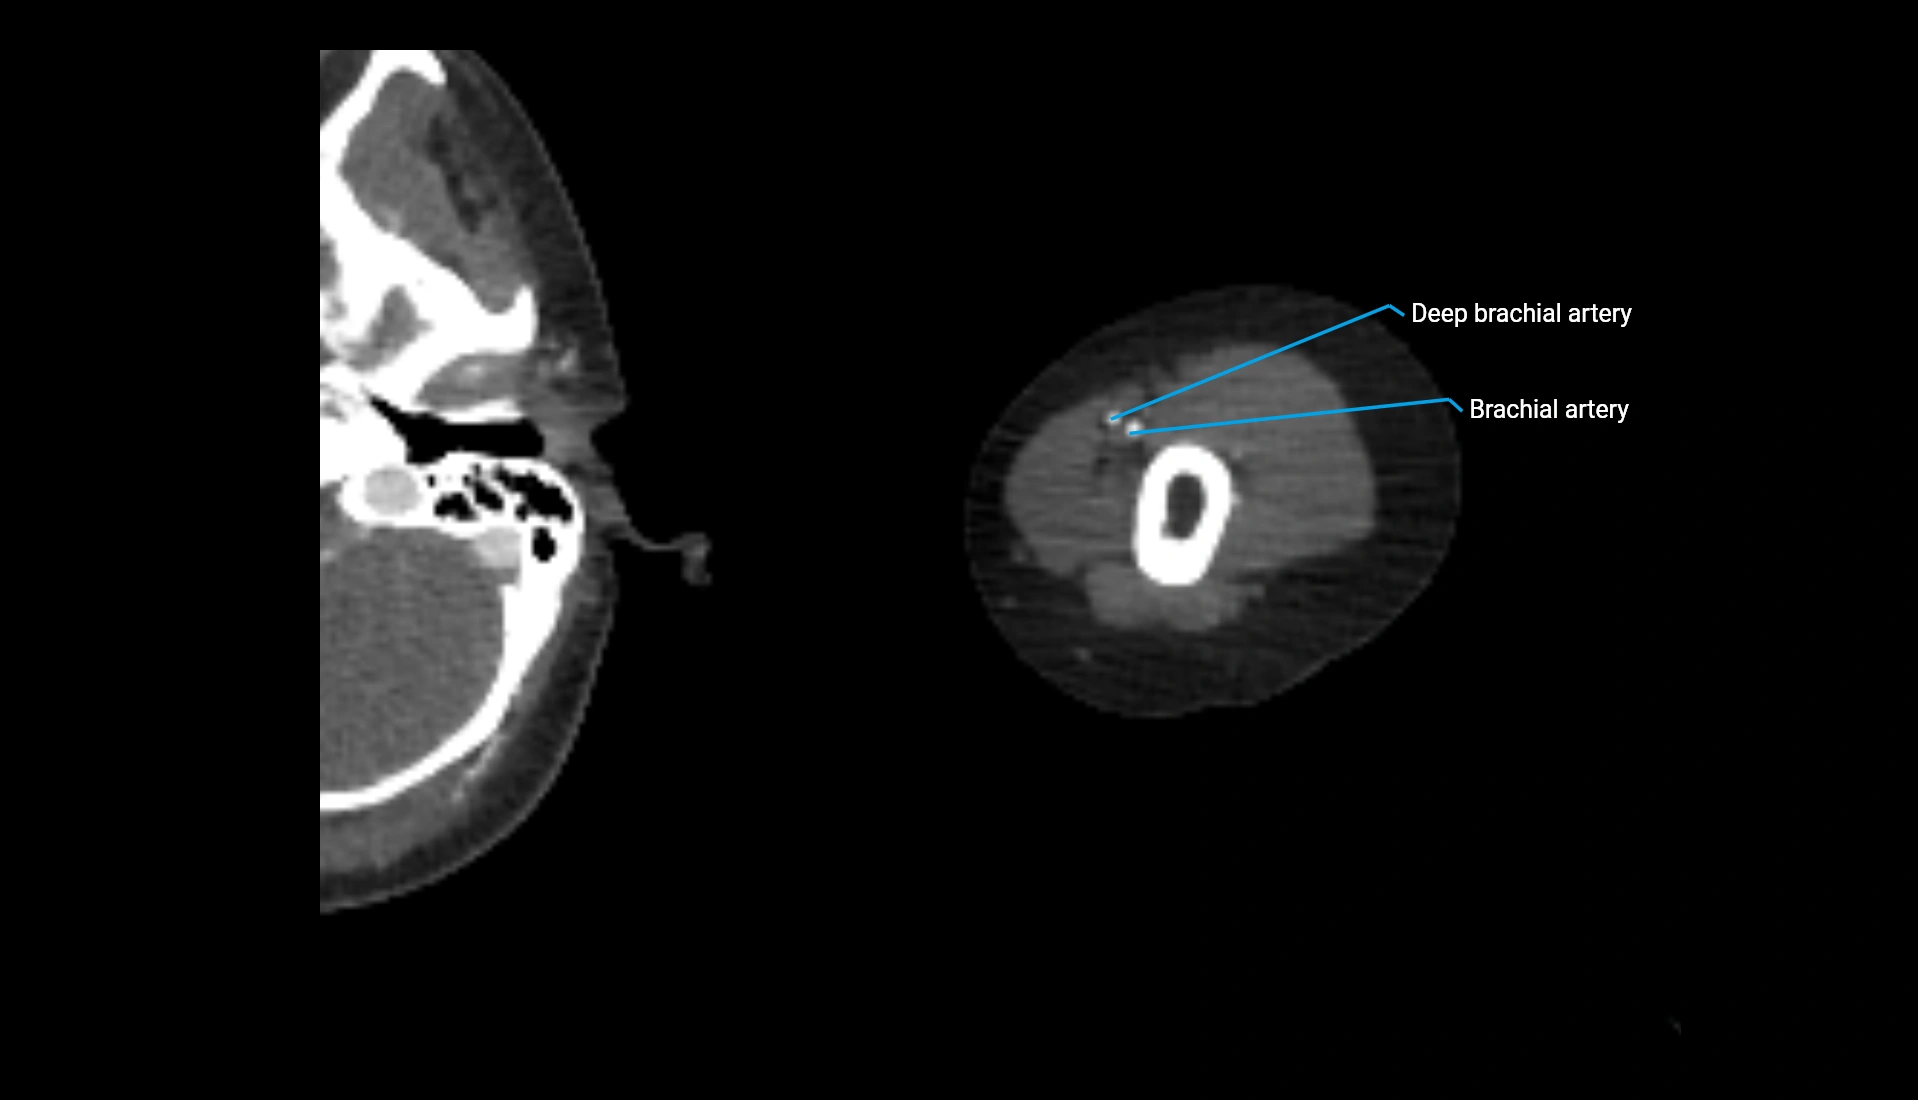

CT Appearance

Non-Contrast CT:

• Cortex: High-density, sharply defined

• Subchondral bone: Dense cancellous matrix

• Articular surface: Smooth concave contour articulating with the capitellum

• Excellent for evaluating bone integrity, alignment, and subtle fractures

Post-Contrast CT:

• Bone: No enhancement

• Joint capsule and synovium: Mild enhancement outlining the joint

• Improves contrast between soft tissues and bony margins

• Useful in detecting subtle joint abnormalities or postoperative changes